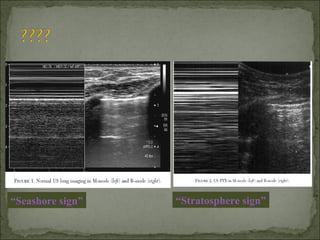

Absence of “lung sliding” as assessed on the time-

motion view

Demonstration of a "lung point" on the time-motion

view

Absence of vertical comet-tail artifacts

USGUSG

 95% sensitivity95% sensitivity

 100% specificity100% specificity

“Seashore sign” “Stratosphere sign”

Normal Abnormal